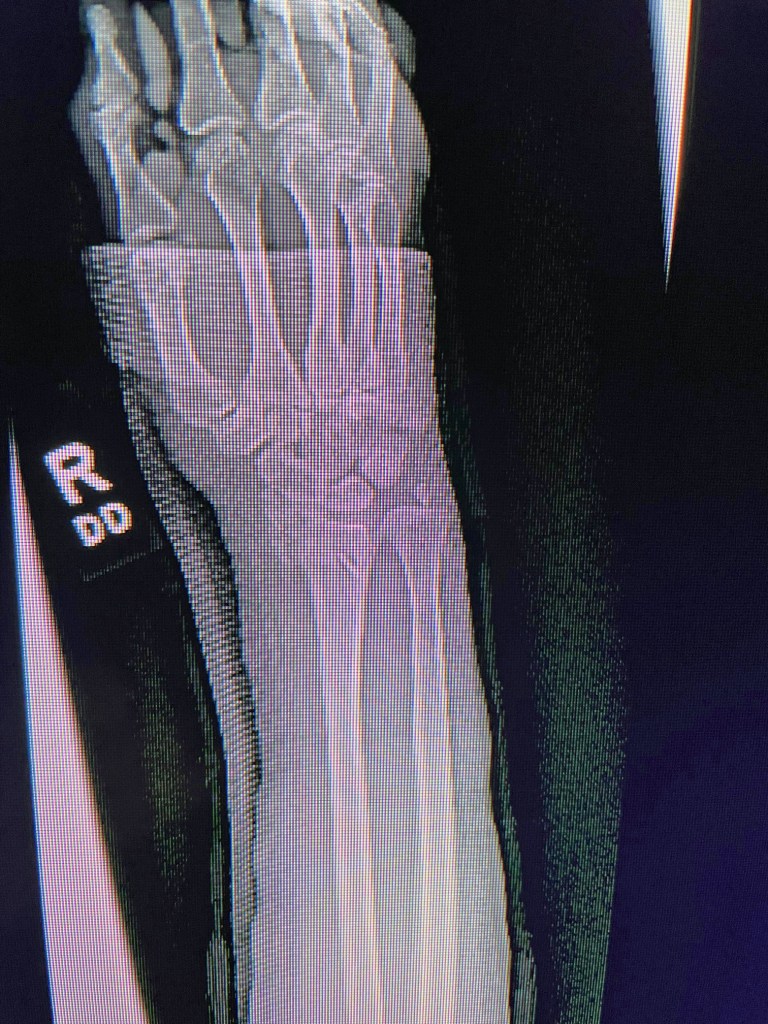

Could it be, this personal neglect of our mother’s body rebounded against our own? For at the end of June in Boston, where I’d come to collect what things she’d left, I fell and broke my right wrist on a pickleball court about three minutes into my first lesson. Surprised out of a lucky and relatively doctor-free lifestyle, my body had to breast a flash flood of x-rays and forms and consultations and administrations of surgical drugs; a piece of metal was installed. Getting its bone density checked just lately by a radiologist, my body was lying flat on an exam table while a curious remote-operated contraption devoured the secrets of its insides from above. Meanwhile, my sister broke a tooth and had to get a crown: a summer, this, to be remembered as the one when our bodies reenacted our mother’s body’s final helpless consignment to the hands of competent strangers.